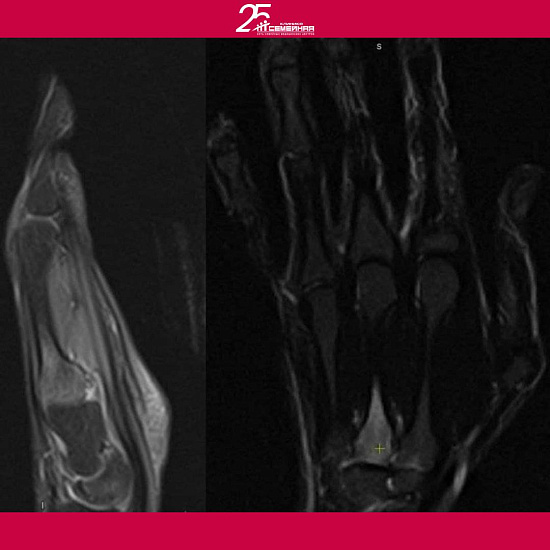

Тогда Ойбек Тургунхужаев вместе с Сиденковым Андреем Юрьевичем − травматологом-ортопедом решили выполнить МРТ и МСКТ кисти.

Травматолог-ортопед Сиденков Андрей по данным МРТ и МСКТ диагностировал отек 3 пястной кости − остеоид-остеому левой кисти.

Это доброкачественная, медленно развивающаяся опухоль кости, ведущим симптомом которой является выраженная боль по ночам, интенсивность которой нарастает по мере развития опухоли.